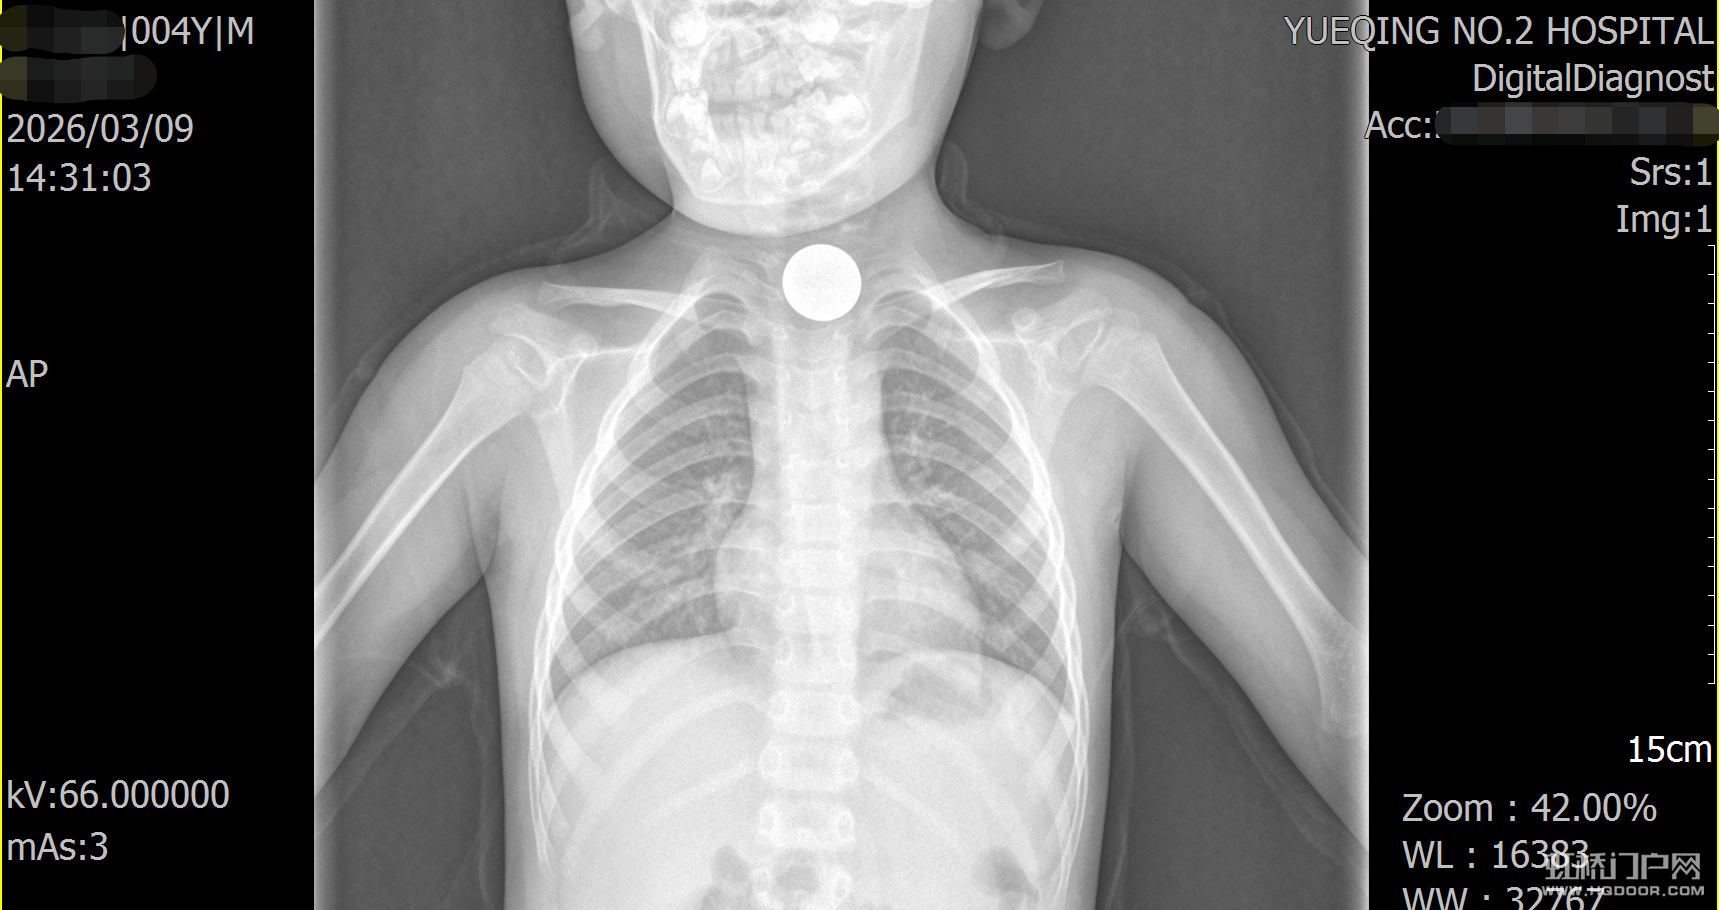

虹桥一名4岁孩子误吞一元硬币,卡在食管长达两个多月,家长一直没察觉。直到孩子频繁喊胸口不舒服,到二医检查才发现。孩子饱胃且异物滞留过久,手术风险极高,好在医院内镜科与麻醉科联手,仅用2分钟就成功取出硬币。真的太惊险了,这么小的小孩家长一定要看好啊